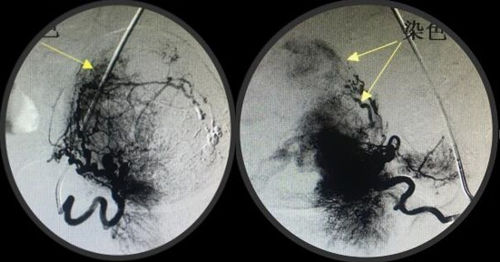

经人介绍来到乐鱼在线登录入口介入科,经李建国主任术前评估,患者无介入手术禁忌症,于4月16日早9点行介入手术。术中采用右肱动脉穿刺、超选择双侧子宫动脉造影栓塞术,手术顺利历时约40分钟,成功保全了子宫。术后患者步入病房,避免了因卧床制动而形成下肢深静脉血栓的风险...